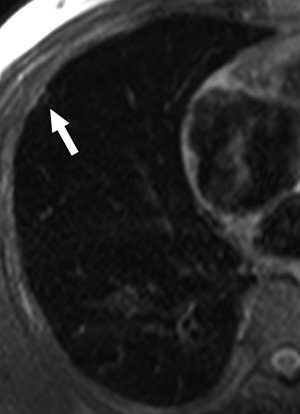

| A 68-year-old woman with focal organizing pneumonia in right middle lobe of lung. Above, dynamic MR image before IV injection of gadopentetate dimeglumine. Below, dynamic MR image obtained three minutes after IV injection of gadopentetate dimeglumine shows slightly heterogeneous enhancement that is strongest in early phase (three minutes = time at maximum enhancement ratio). Signal intensity before and three and six minutes (time at maximum enhancement ratio plus three) after contrast injection was calculated by each region of interest. Maximum enhancement ratio, 126%; slope, 42%/min; washout ratio, 15%. |